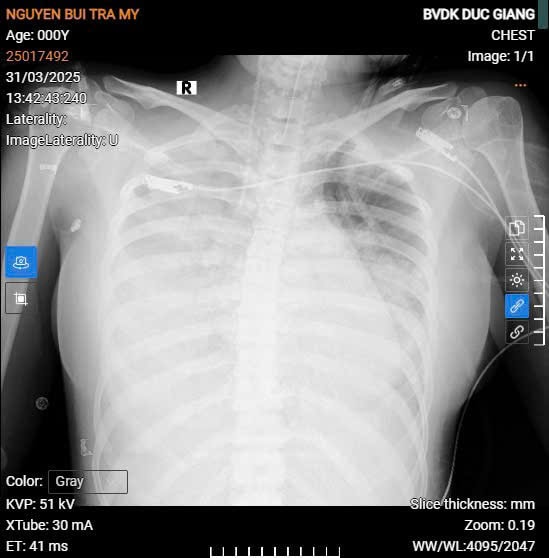

Ngay lập tức, bệnh nhân được chuyển vào Khoa HSTC-CĐ trong tình trạng nguy kịch. Các bác sĩ đã triển khai đồng bộ các biện pháp hồi sức chuyên sâu: thở máy xâm nhập, sử dụng thuốc vận mạch, lọc máu liên tục và phối hợp kháng sinh sớm, đúng mục tiêu điều trị.

Sau 5 ngày điều trị tích cực, bệnh nhân thoát sốc, phổi cải thiện, ngừng vận mạch. Hai tuần sau, bệnh nhân có thể tự thở và trò chuyện.